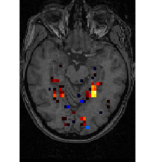

face

vs house

TV-l1

Graph-net

Social sparsity

Finally, an important aspect of the brain decoders is whether they segment well the brain regions that support the decoding. Such a question is hard to validate, yet there is evidence that TV- is a good approach [5]. Fig. 2 displays the decoder maps for the object-recognition tasks. For these tasks, we expect prediction to be driven by the functional areas of the visual cortex [27]. Indeed, the maps outline regions in known visual areas. The graph-net maps are much more scattered and less structured than the others. Conversely, the social sparsity maps are sparser and outline a smaller number of clusters.